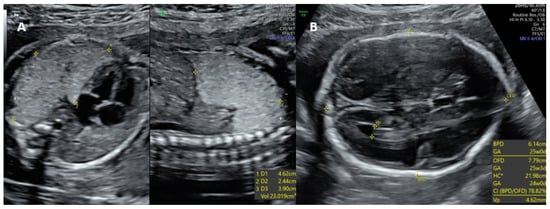

In the general prognosis of CCAM, the size of the lesions and the underlying growth characteristics are more relevant than the histologic type. Recent studies are consistent with the literature and show that lung masses reach their maximum size between 24 and 28 weeks of gestation [4]. The microcystic subtype, which corresponds to a solid echogenic mass, tends to regress spontaneously after 26 to 28 weeks of gestation. However, the macrocystic subtype, which presents with single or multiple cysts 5 mm or larger in diameter, usually does not regress because of fluid accumulation within the cysts, resulting in an increased risk of pulmonary hypoplasia, pleural effusion, fetal hydrops, and subsequent fetal death [7] (Figure 3).

Figure 3. Two-dimensional ultrasonography. Complications of congenital adenomatoid cystic malformation. (A) Axial plane at the level of the four-chambers view; mediastinal shift. (B) Sagittal thoraco-abdominal plane; hydrops. (C) Polyhydramnios. Source: the authors.